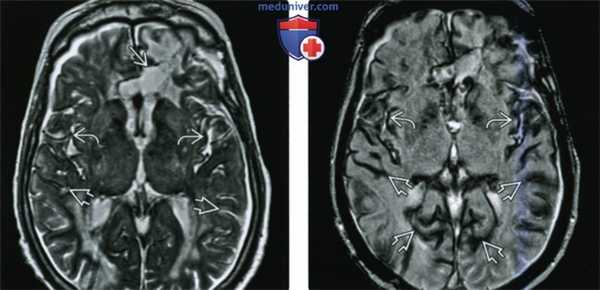

(а) MPT, Т2* GRE, аксиальный срез: у мужчины 57 года с двусторонней нейросенсорной тугоухостью и наличием в анамнезе давней резекции олигодендроглиомы лобной доли на поверхности ствола мозга, ЧН IX-XI, в области листков мозжечка , а также сосудистого сплетения IV желудочка определяются гипоинтенсивные наслоения.

(б) Более краниальный аксиальный срез: у того же пациента определяется поверхностный сидероз (ПС) VII и VIII ЧН, а также в области эпендимы IV желудочка.

(а) MPT, Т2* GRE, более краниальный аксиальный срез: у этого же пациента определяется диффузный ПС, локализующийся вдоль обеих сильвиевых борозд, а также в области поверхности среднего мозга, вершины червя мозжечка.

(б) MPT, Т2* GRE, более краниальный аксиальный срез: вдоль поверхностей обеих сильвиевых борозд, а также межполушарной борозды определяются наслоения. Обратите внимание на гемосидериновое окрашивание эпендимы, сосудистых сплетений боковых желудочков. (а) МРТ, Т2-ВИ, аксиальный срез: у мужчины 60 лет с прогрессирующей атаксией, двусторонней нейросенсорной тугоухостью определяется ПС, визуализируемый как «утолщение» и «черное очертание» обоих ЧН VIII. Обратите внимание на мозжечковую атрофию, увеличение размеров IV желудочка, усиление фолиации мозжечка.